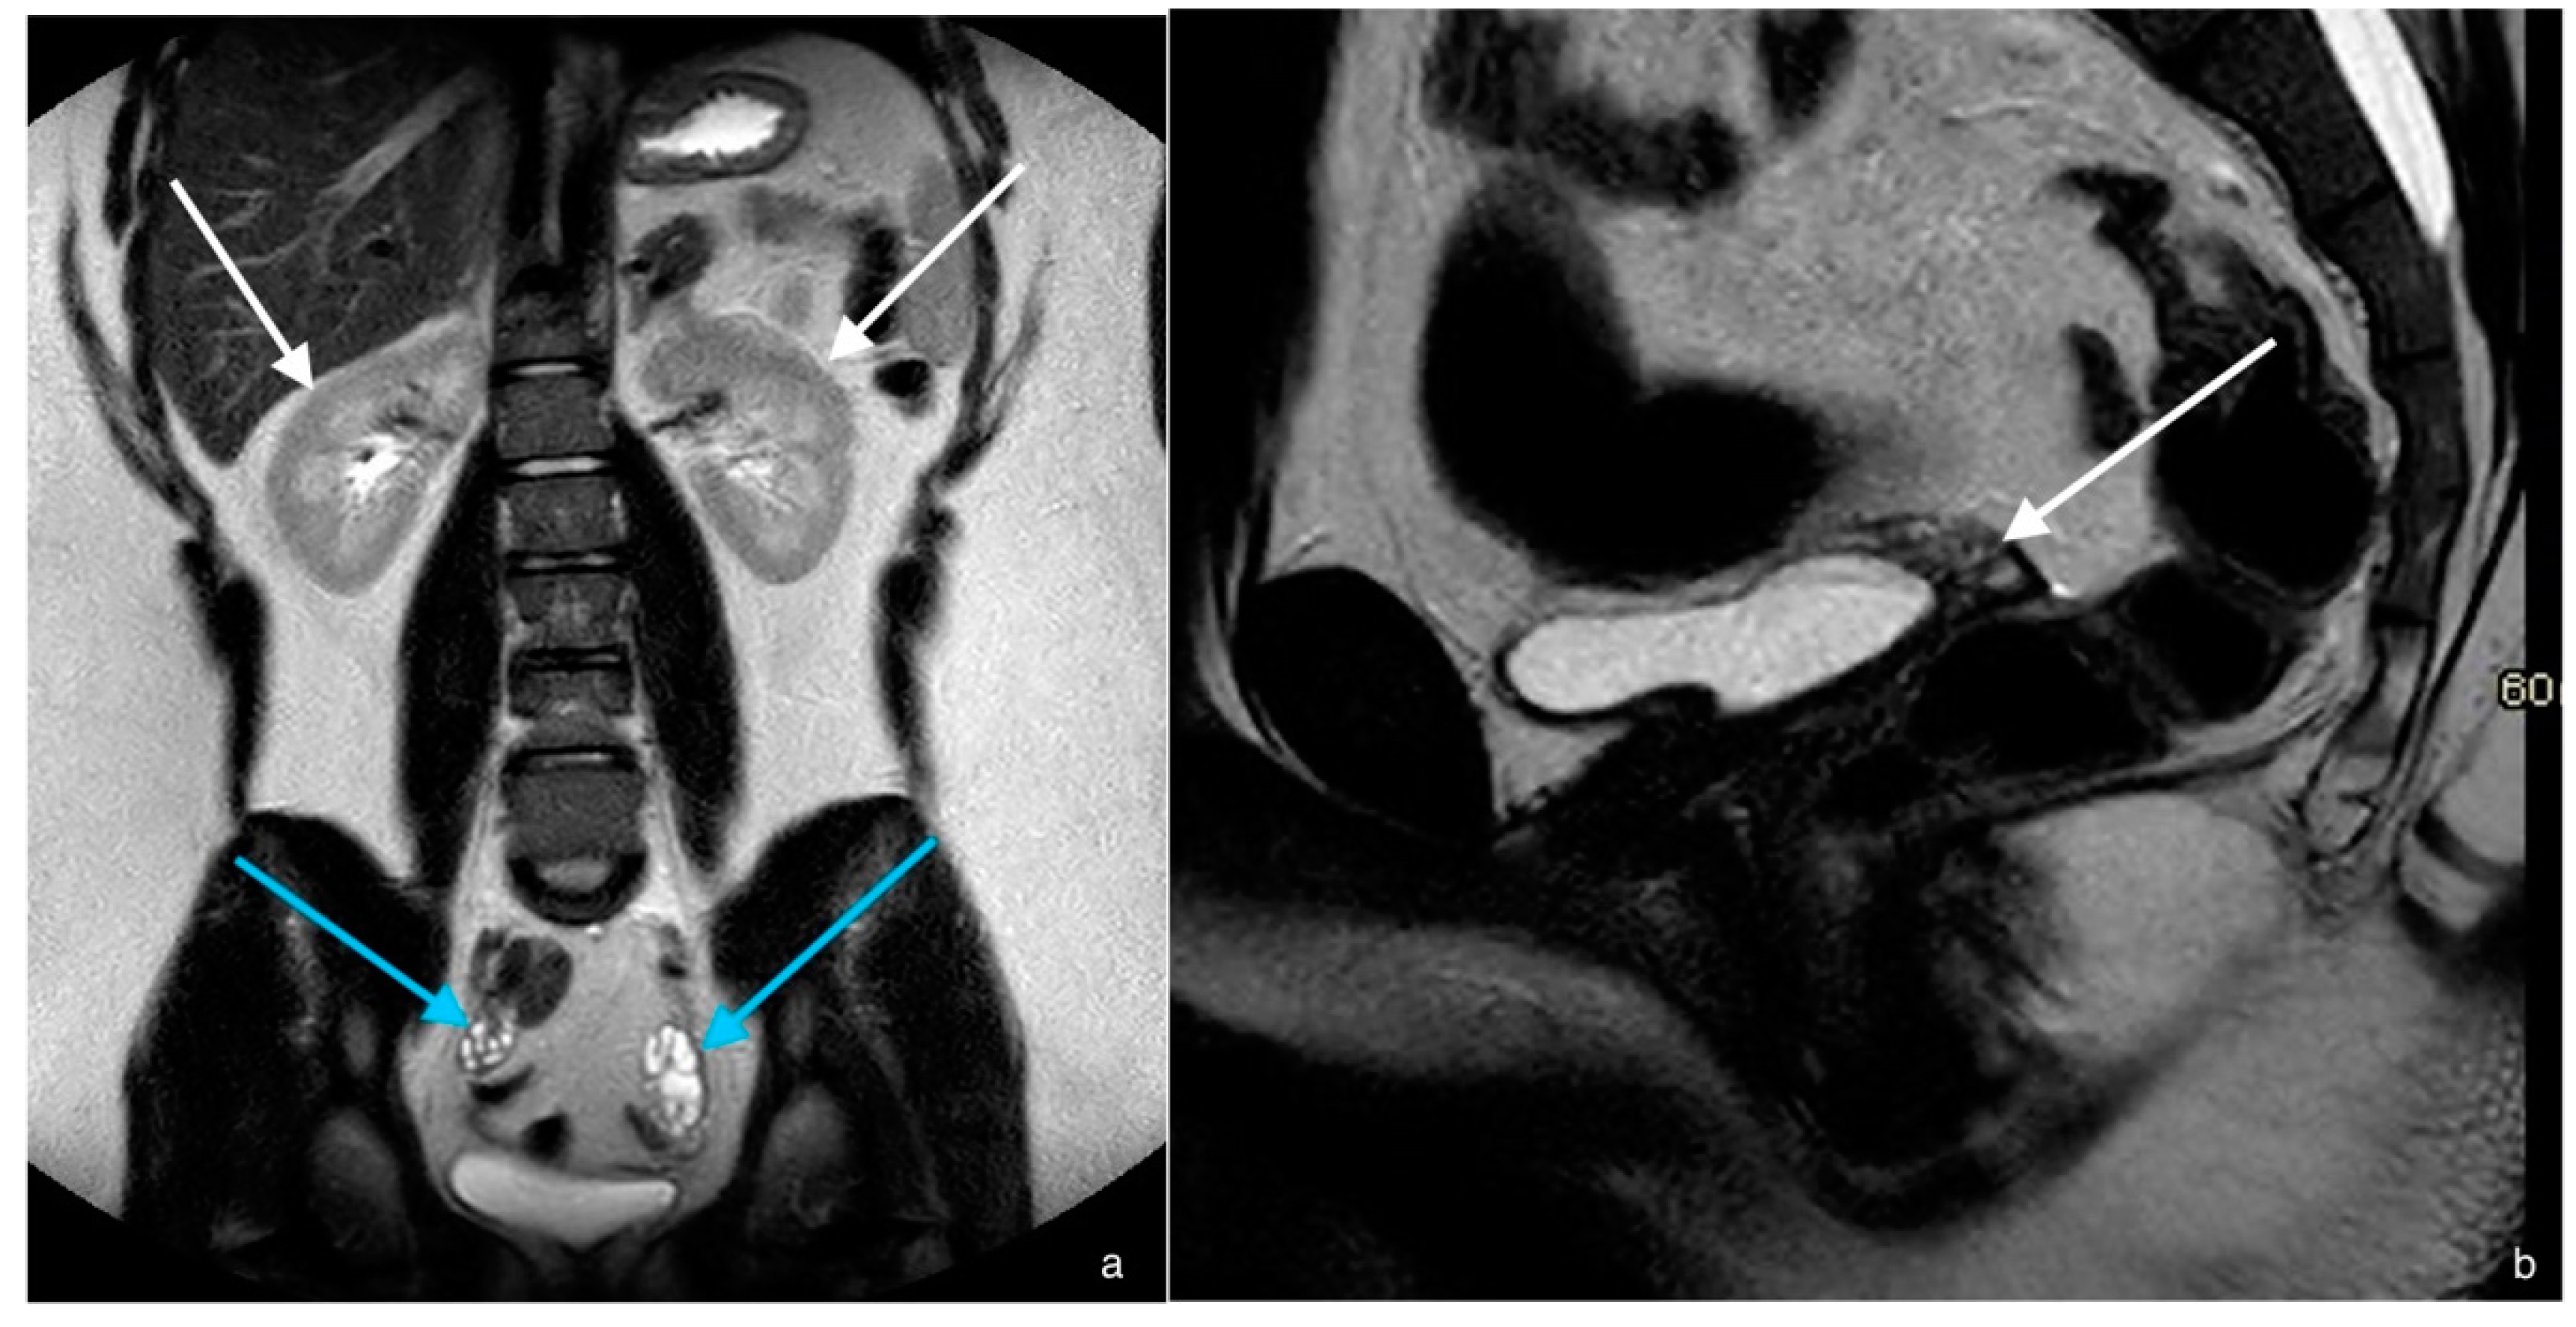

2. Case 1

| MRI report on primary investigation | Absent uterus, impression of hypoplastic vagina. Normal multicystic ovaries | Absent uterus and presence of a short vagina. Normal ovaries | Normal multicystic ovaries and a small uterus of 2.3 × 1.3 cm, described as rudimentary uterus | |

| MRI after referral | Lipofibromatous tissue at location of the uterus, no endo- myometrial or cervical structures. Normal multicystic ovaries | Underdeveloped Müllerian structures. Gonads with (ovo)testicular aspect | Small uterus with normal endo- and myometrial tissue, normal multicystic ovaries | |